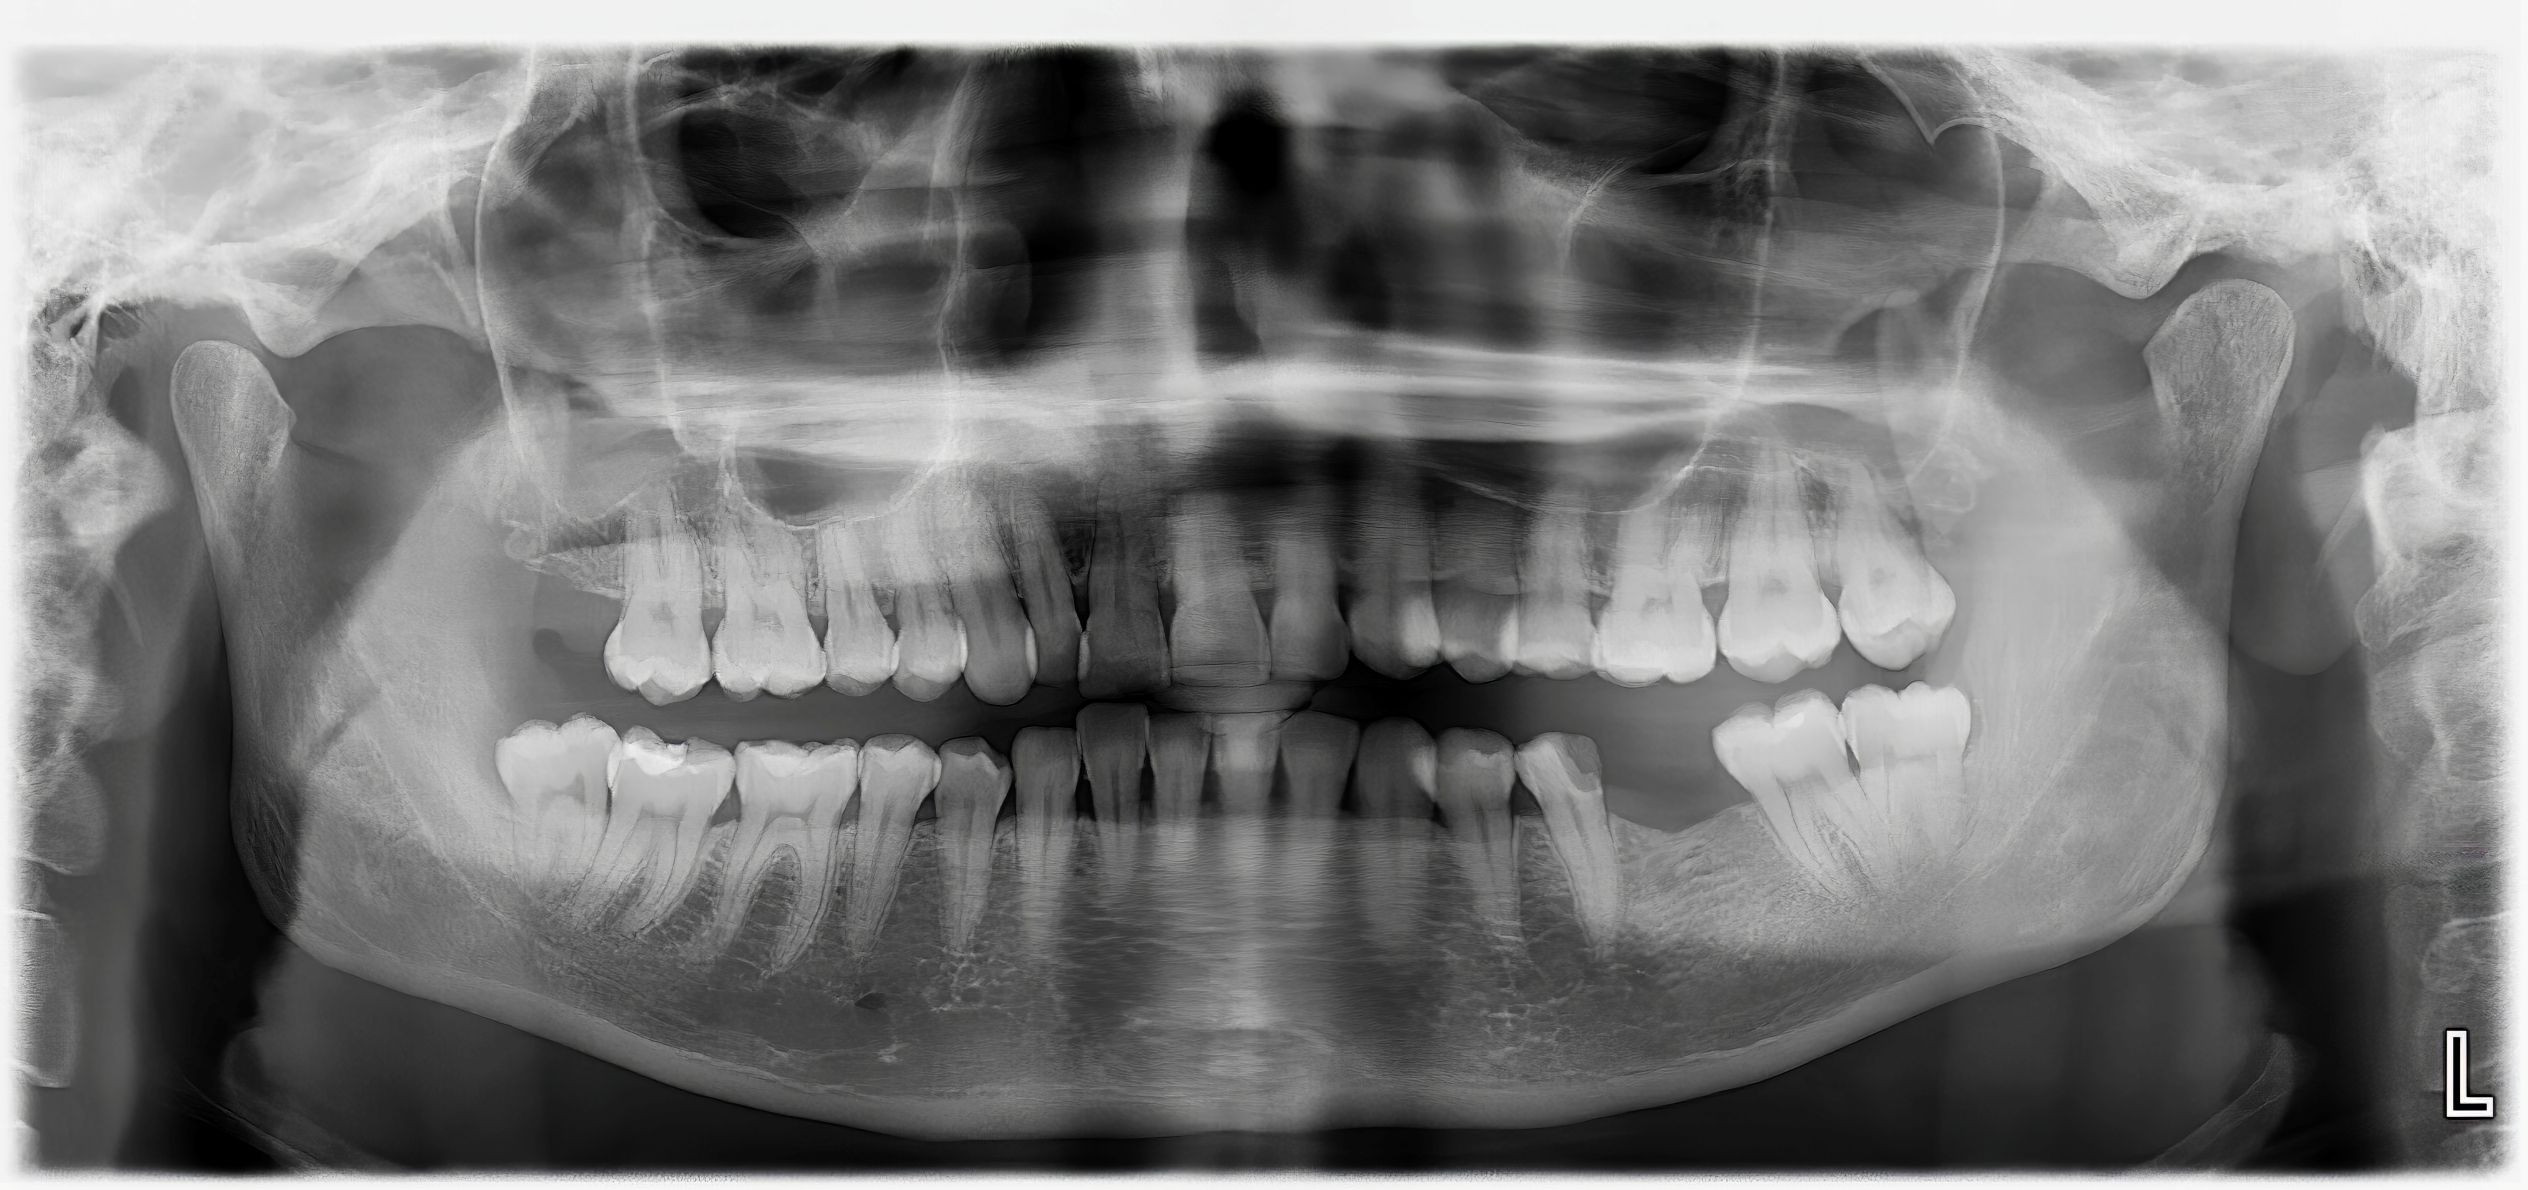

When you first visit a new dentist, they’ll typically recommend a comprehensive baseline examination, including a full mouth series or panoramic X-ray, along with bitewing X-rays. This initial set creates a complete picture of your oral health and serves as a reference point for future visits.

For adult maintenance, healthy patients generally need bitewing X-rays every 12-18 months, with a full mouth series recommended every 3-5 years. However, this schedule may be adjusted based on your oral health history and current conditions.

Children require special consideration in X-ray scheduling. Most dentists begin taking X-rays when the child’s baby teeth start touching, typically around age 4-6. During cavity-prone years and periods of rapid development, more frequent imaging helps monitor tooth emergence and identify potential problems early. Panoramic X-rays become particularly important during orthodontic planning phases.